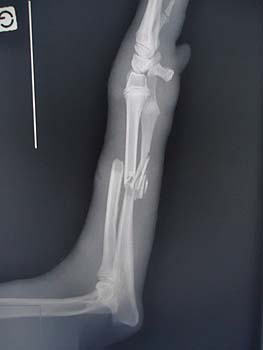

Vorstellung von Grace: Grace

wurde von einer französischen Tierschützerin aus einem Tierheim

geholt, wo sie mit einem dreifachen Beinbruch gelandet war. Im

Tierheim wäre ihr Beinbruch kaum behandelt worden und Grace wäre wohl

eingeschläfert worden. Das Bein wurde dann Anfangs März

operiert, zur Zeit hat Grace eine Metallplatte im Bein, die nach

einigen Monaten dann wieder entfernt werden muss.